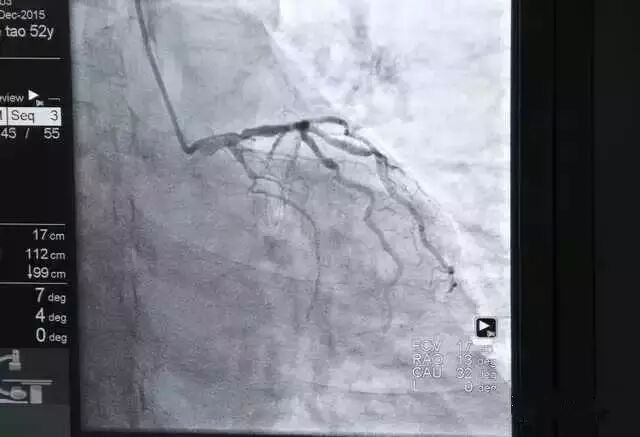

使用环柄注射器推入造影剂,通过X光透视可在电脑屏幕上显示血管形状;